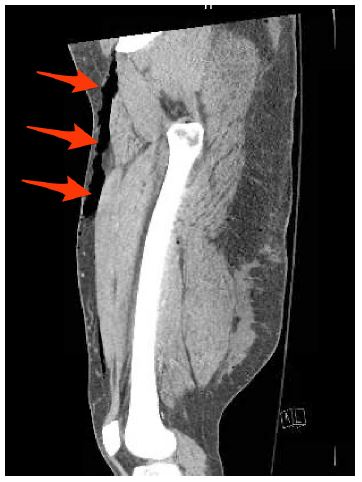

Follow up CT imaging (Figure 3) confirmed extensive air and fluid throughout the subcutaneous soft tissues of the right thigh consistent with a high energy crush mechanism.

Figure 3: Coronal CT image of the right thigh. Red arrows confirm the Morel-Lavalee lesion noted on plain film imaging.